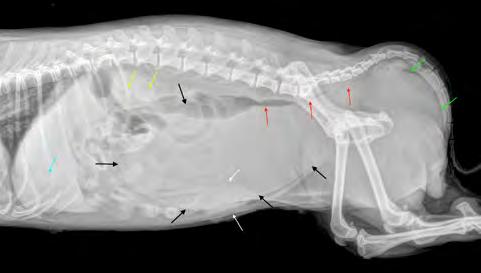

Después de la cirugía se analizaron las radiografías postoperatorias, realizándose las mismas mediciones que en la planificación, y observándose cómo los valores obtenidos tras la cirugía se correspondían con los valores planificados (Fig. 5). Se colocó un vendaje postoperatorio sencillo durante 14 días, para evitar la manipulación del área quirúrgica por parte de la pa-

ciente, lo que facilitó una cicatrización correcta de la herida y una buena recuperación del animal, que comenzó a caminar con normalidad a los pocos días de la intervención (Fig. 6).

En cuanto a la evolución, resulta vital realizar radiografías de seguimiento postoperatorio con cierta periodicidad (Fig. 7). Esto nos permite tener un control adecuado del animal y actuar lo antes posible si se presentase algún contratiempo. En el caso que nos

ocupa, además de las radiografías postoperatorias realizadas tras la cirugía correctiva y las efectuadas antes de retirar los implantes, se realizó una TC de revisión tras la extracción de los mismos (al año y dos meses de su colocación), observándose en 3D una buena remodelación y alineación de los huesos. Si comparamos estas imágenes de TC con las primeras, es decir, con las de la planificación quirúrgica antes de la corrección, se puede observar que la superposición de ambas TC muestra una alta precisión en lo que respecta al resultado obtenido (Fig. 8).

Figura 5. Proyecciones radiográficas craneocaudal y mediolateral posquirúrgicas. Las radiografías muestran el resultado tras la cirugía.

Figura 7. Proyecciones radiográficas (A) craneocaudal y (B) mediolateral a los 4 meses de la cirugía. Las imágenes muestran la avanzada consolidación de la ostectomía.